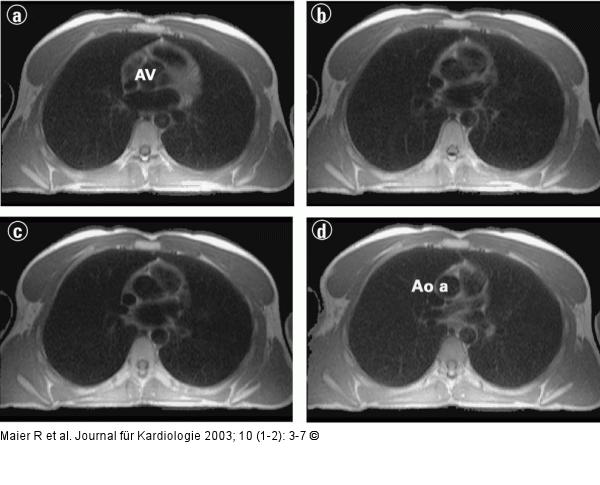

Abbildung 7a-d: Kardiale Magnetresonanztomographie Transversale Schnitte vom Zwerchfell bis zum Aortenbogen |

Abbildung 7a-d: Kardiale Magnetresonanztomographie

Transversale Schnitte vom Zwerchfell bis zum Aortenbogen |